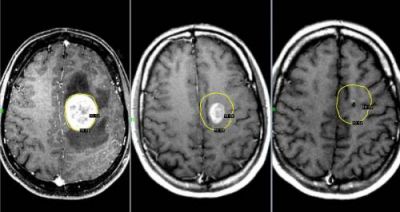

Опухоли мозга

Злокачественные опухоли характеризуются быстрым прорастанием в другие ткани с их последующей трансформацией. При этом метастазы могут наблюдаться сразу в нескольких участках мозга.

Такие опухоли плохо лечатся, а на поздних стадиях их развития спасти человека практически невозможно.

Характер болевых ощущений — постоянный, по мере развития заболевания продолжительность приступов увеличивается. Когда человек двигается, болевые ощущения усиливаются. Сначала они локализуются в области опухоли, потом, по мере увеличения внутричерепного давления, переходят в лобную и затылочную часть. Наиболее сильный дискомфорт наблюдается в ночное и утреннее время из-за скопления жидкости. Вены не справляются с оттоком крови, поэтому к болям прибавляются отёчность и застои. Боли давящие, распирающие, пульсирующие.

К головным болям затем добавляется рвота. При физической нагрузке или кашле болевые ощущения усиливаются, появляется двоение в глазах, временами исчезает зрение. Голова кружится, у пациента нарушается координация движений. Могут неметь конечности, ослабляется тонус мышц.

Иногда бывают эпилептические припадки, путается сознание.

Диагностирование

Для диагностики используется МРТ мозга, ПЭТ, КТ мозга, ангиография и другие методы.